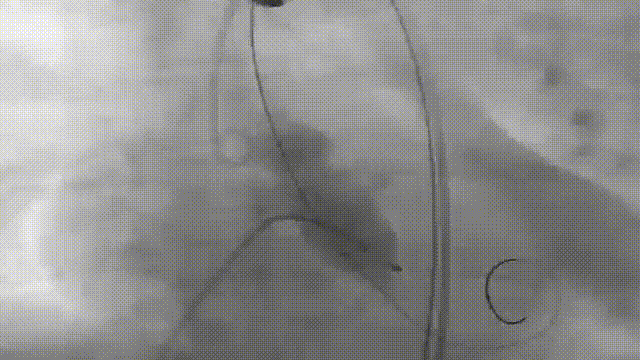

患者全麻后,右侧股动脉建立主入路,主动脉根部造影显示主动脉瓣明显钙化伴重度狭窄。直头导丝跨瓣后,在超硬导丝支撑下,瓣膜输送系统顺利跨瓣。在180次/分快速心室起搏下,确定降压至50mmHg后选择22mm球囊进行预扩张。根据术前评估及球囊预扩情况,最终选择进行植入。

主动脉根部造影

22mm球囊预扩

0位释放

瓣膜完整形态